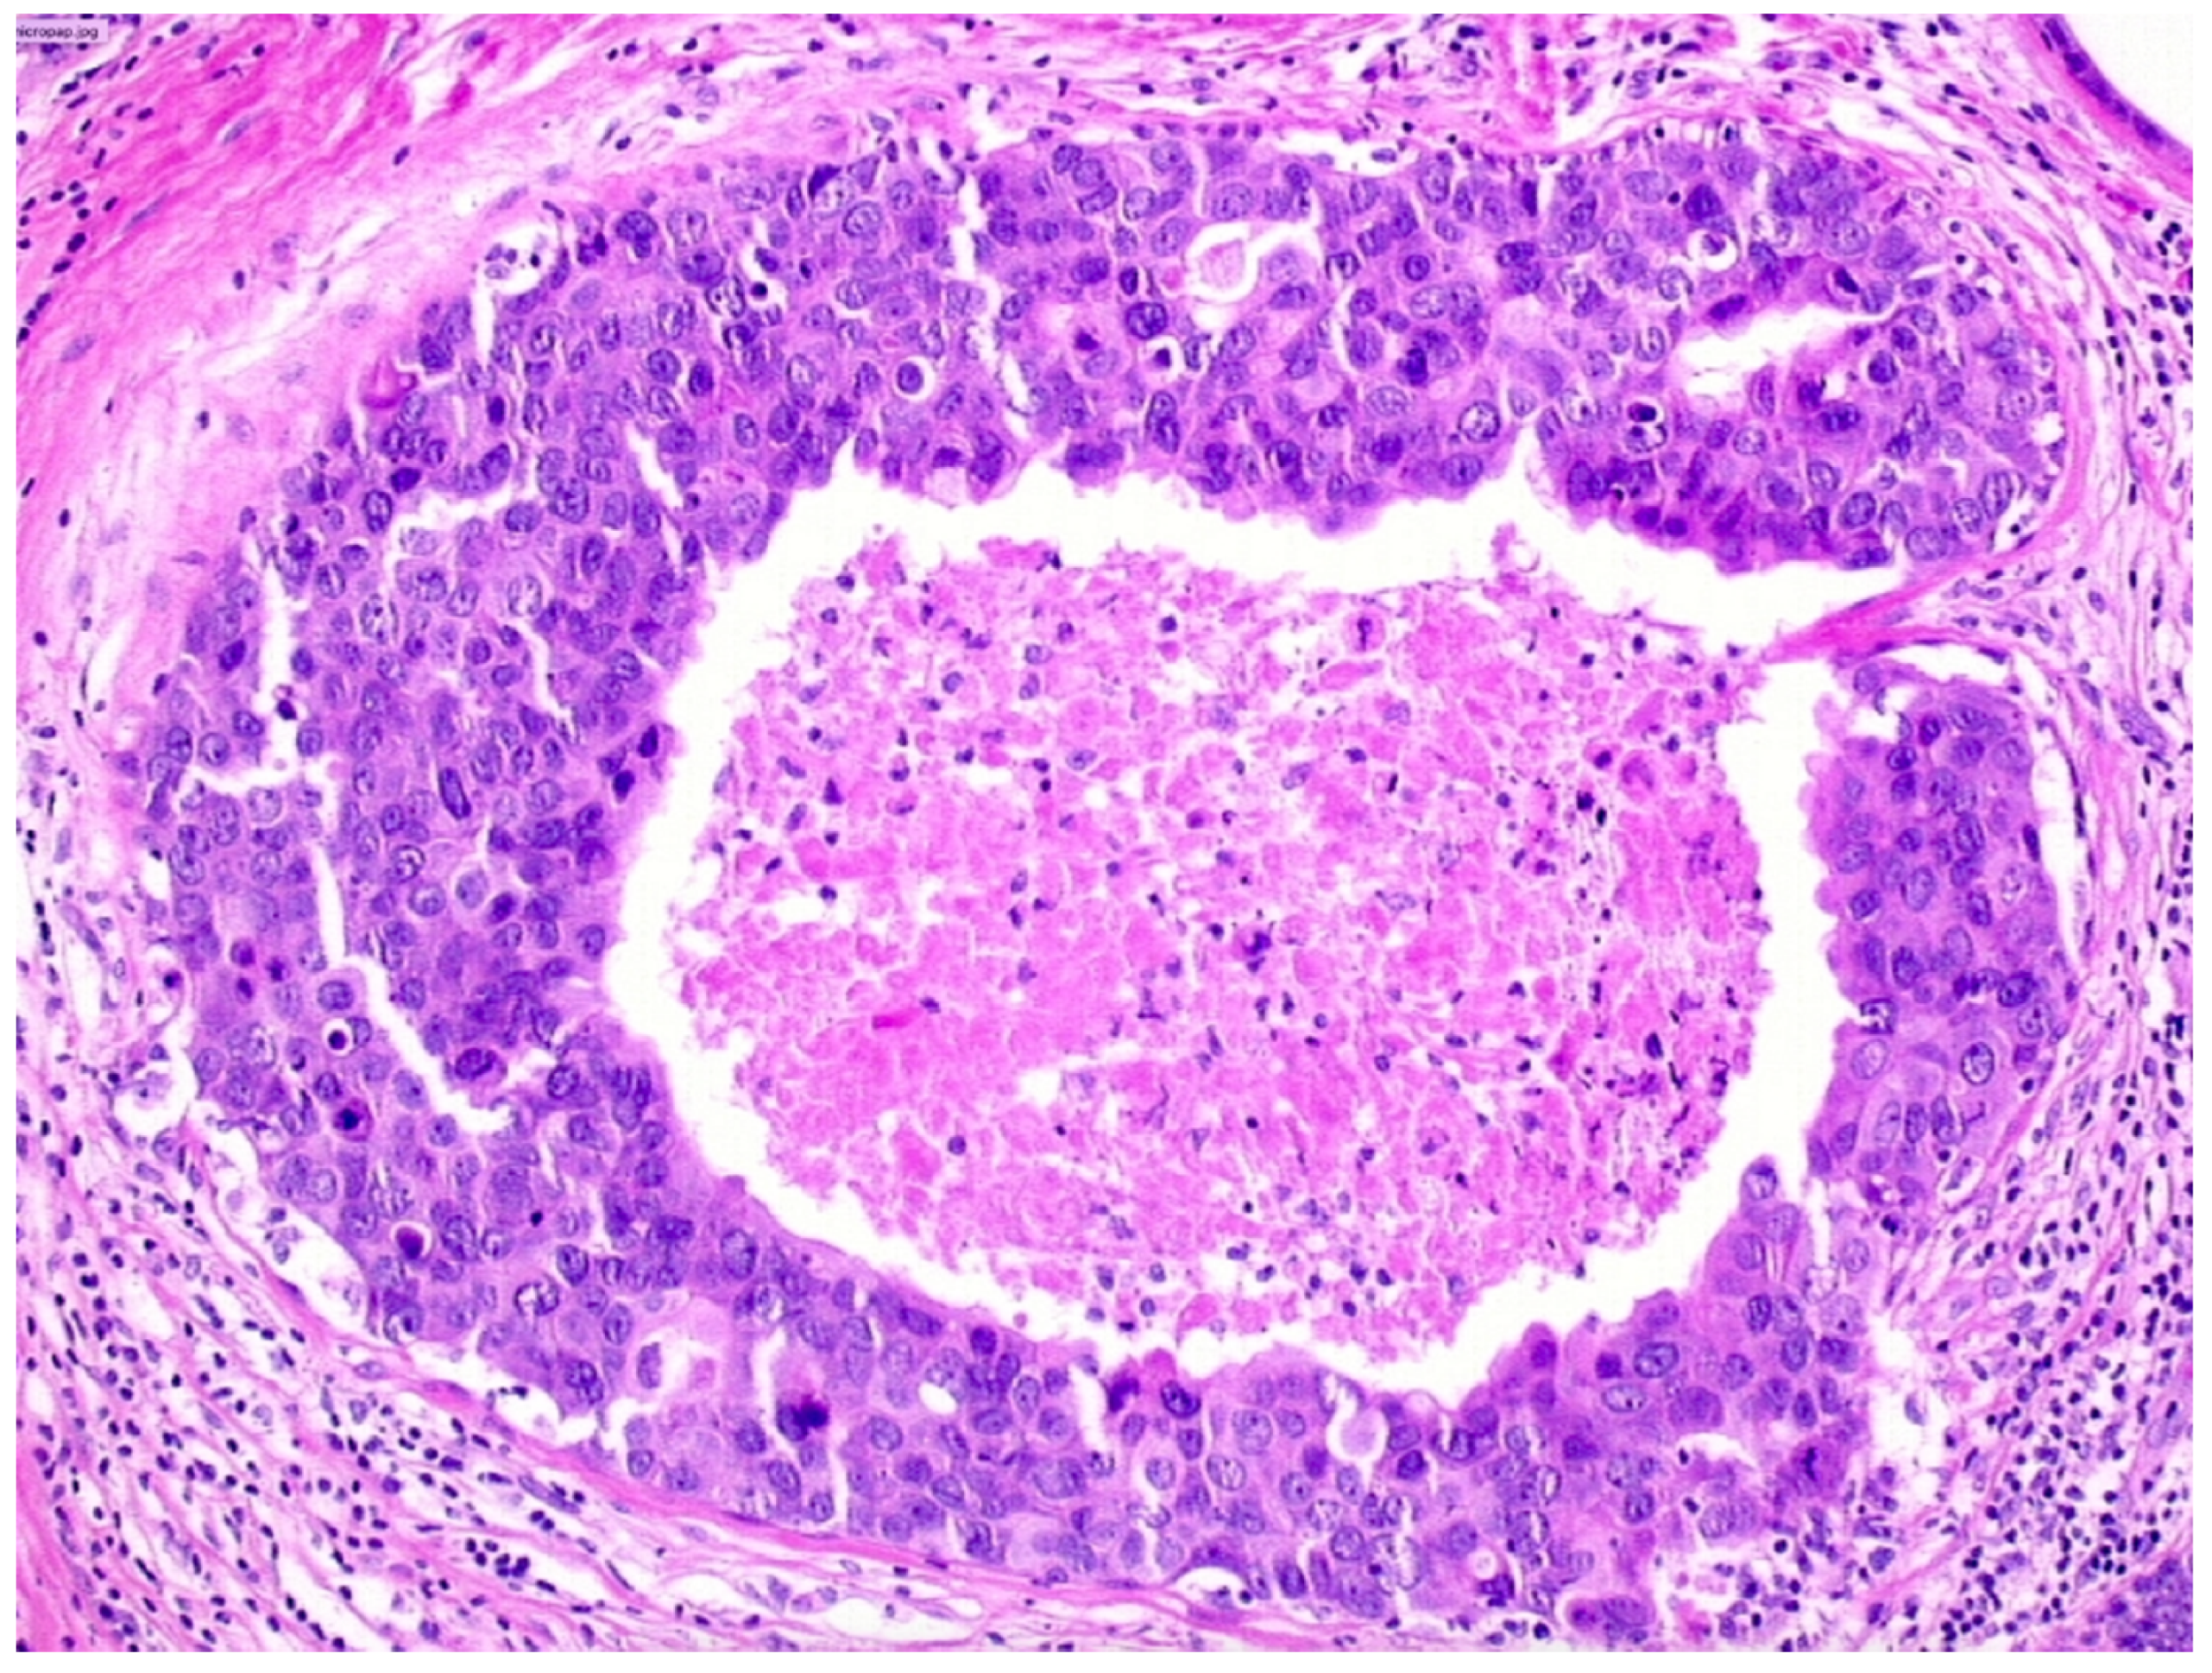

We observed that 1262 patients received the diagnosis of DIN2 (intermediate-grade DCIS, Figure 3)—15.1% (191/1262) of them were upgraded to invasive cancer. The overall mean diameter of the DIN2 lesions was 20 mm.

We reported, post-VABB, complete removal of the lesion in 420 out of 1262 patients with DIN2 diagnosis. Among them, we reported 33 cases of invasive carcinoma on surgical specimen, and thus 7.8% (33/420) of intermediate-grade DCIS cases with no residual lesion were upgraded to invasive cancer.

Patients with diagnosis of intermediate-grade DCIS showing complete removal of the lesion experienced a significantly lower upgrade rate compared to those showing mammographically detectable residual tumor after VABB (p-value < 0.05).

Figure 3. Ductal carcinoma in situ of intermediate nuclear grade (DIN2).